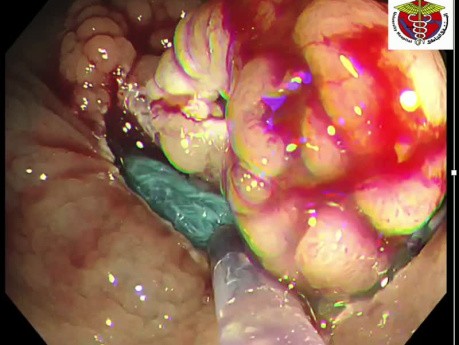

Cierre de perforación: el arte del clipado

Un caso de perforación incompleta tras procedimiento endoscópico en colon transverso. Se utilizaron hemoclips, suturando completamente el lecho de resección. El paciente comenzó a recibir antibióticos...